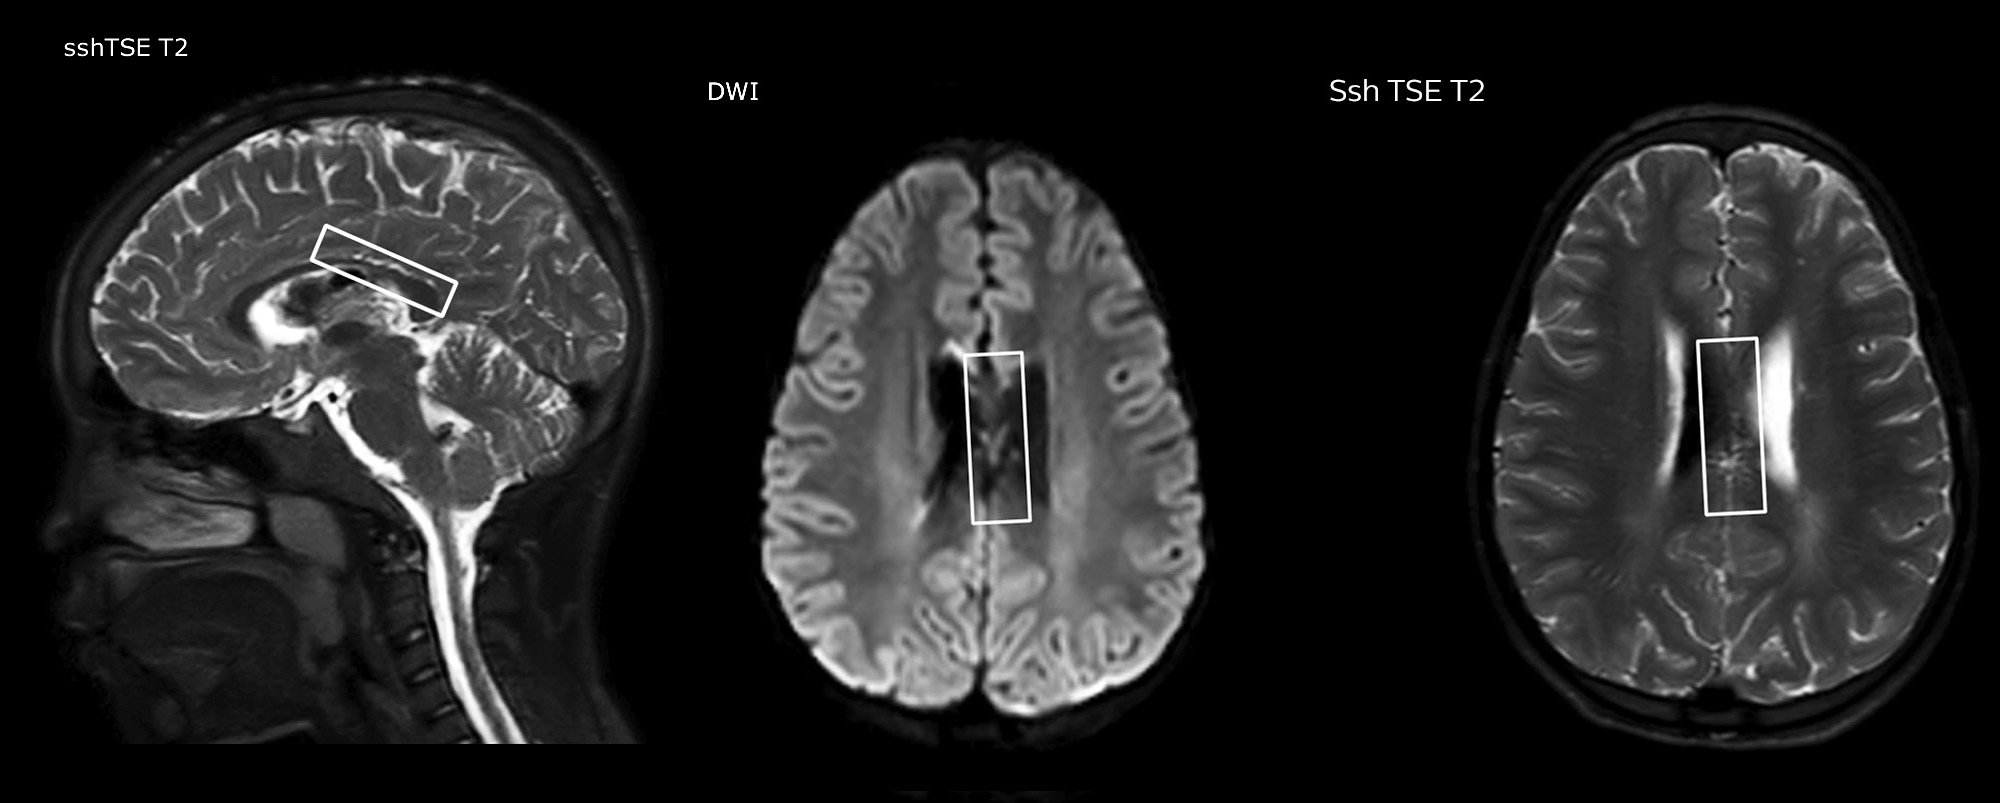

Philips mDIXON TSE is a two-point DIXON technique that separates water and fat signals, for time-efficient fat-free imaging, even in challenging neuro anatomy. “mDIXON TSE has been one of the most significant improvements in imaging sequences that we have utilized to date at PCH,” says Dr. Miller. “Its multi-parametric acquisition allows us to obtain fat suppressed images and equivalent non-fat suppressed T2 images all in the same sequence. In addition, prior methods of fat suppression could be artifactually corrupted by poor patient anatomy or poor operator application, but with mDIXON we now have a robust and reliable method of fat suppression.” Fat saturation is historically challenging at the ends of fields of view, especially in total spine imaging and in difficult patient anatomy such as the lower regions of the neck. “Due to the unique fat suppression capabilities of mDIXON, however, these challenges no long apply,” says Dr. Miller. “We routinely obtain homogeneous fat suppression under virtually all conditions. It has also led to some efficiencies by not having to repeat sequences because of that technical failure.”

“mDIXON TSE has increased our diagnostic confidence in ruling in or ruling out abnormalities in which fat suppression is critical to diagnosis, such as metastatic disease or osseous abnormalities.”

“mDIXON TSE is most useful in patients with lesions or abnormalities in the soft tissues such as the face and neck, and for patients with contrast enhancing abnormalities that are mostly visible with fat suppression,” says Dr. Miller. “All our spine imaging now routinely contains mDIXON water-only T2 images, and this allows us to identify pathology that may be obscured by non-fat suppressed imaging such as injuries of the bone. And it’s not necessary to obtain additional standard TSE T2 images because the in-phase mDIXON images are equivalent to standard TSE T2 images.”